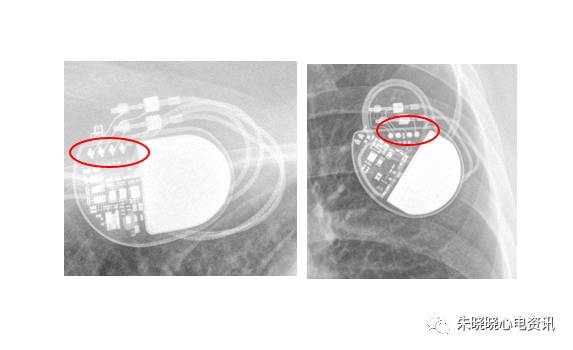

如圣犹达起搏器典型的接线方式是独有的一个长方形线圈(图8),

波士顿科学起搏器部分接线为数条导线并排,可联想为蜈蚣帮助记忆(图9),

图8 圣犹达起搏器

图9 波士顿科学起搏器

图10 波士顿科学起搏器